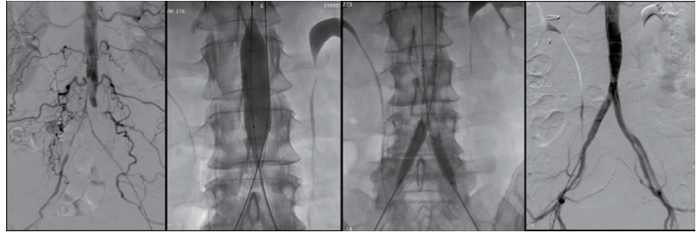

Observe as imagens:

Enunciado 4377375-1

(Arquivo pessoal; imagem usada com autorização)

Assinale a alternativa que corresponde à técnica operatória apresentada nas imag